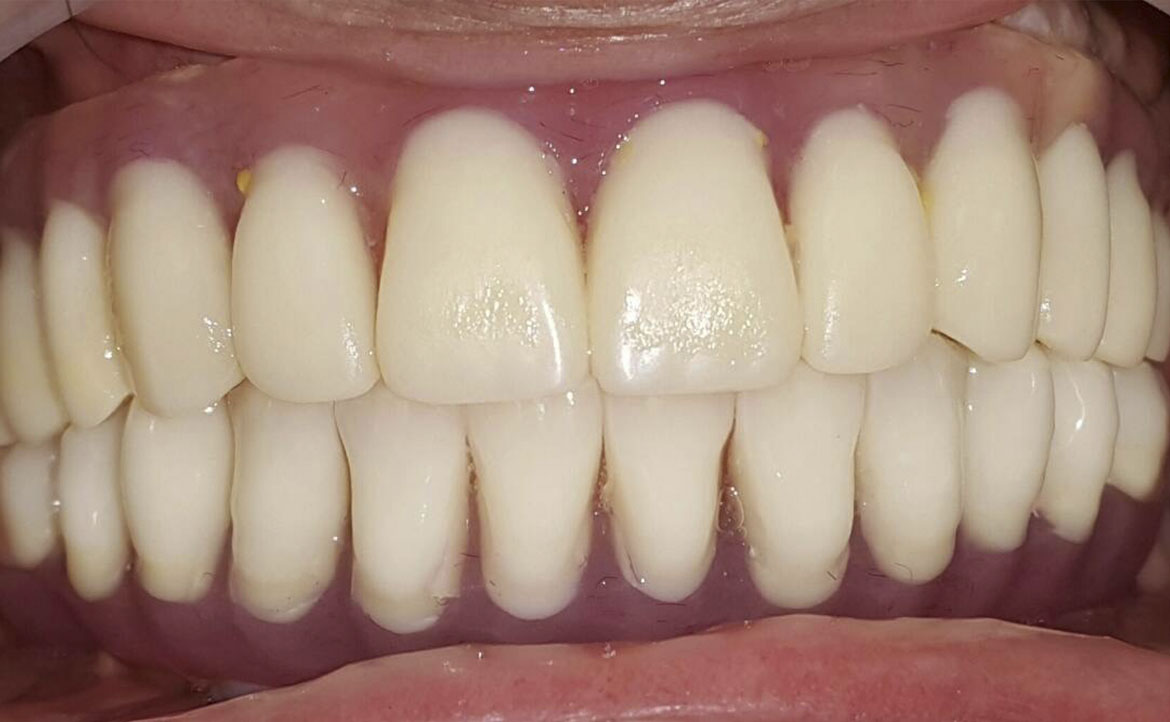

Puntea dentară este cea mai căutată soluție de umplere a spațiilor lipsă a danturii. Asta pentru că timpul de realizare este minim. Puntea este fixată pe dinții învecinați care, pentru o susținere mai bună, inițial sunt șlefuiți. Odată aplicată dantura capătă un aspect estetic natural și, dacă este întreținută corespunzător, are o durată de viață îndelungată.

Pe lângă restabilirea estetică a danturii, puntea dentară împiedică complicațiile care pot apărea de pe urma lipsei unui dinte. Odată aplicată va îndeplini procesul normal de masticație și va îmbunătăți funcția fonetică.